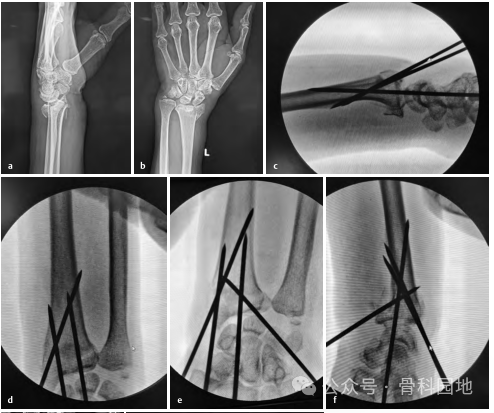

首先进行骨折闭合复位,牵引时须缓慢而持续,通过掌屈和尺偏来矫正背侧和桡侧移位。复位后,将手放在卷起的布单上,保持掌屈和尺偏(下图a,b),并用至少三根经皮克氏针固定。

第一枚克氏针在 Lister 结节进针,以 45°倾斜,瞄准桡骨长轴上近端骨块的掌侧皮层。如果进针点位于Lister结节的尺侧,可能会损伤拇伸肌腱。

第二枚克氏针自桡骨茎突远端 0.5 cm 处进针,克氏针与桡骨轴成 60°角,穿透骨折近端尺侧皮质。

第三枚克氏针在距腕关节线远端0.5 cm处,固定月骨窝骨块,位于第四和第五伸肌室之间。克氏针以 45 °角固定到桡骨的掌侧,如下图a、b 所示。

使用经典经皮克氏针固定桡骨远端骨折,如下图a-e 。